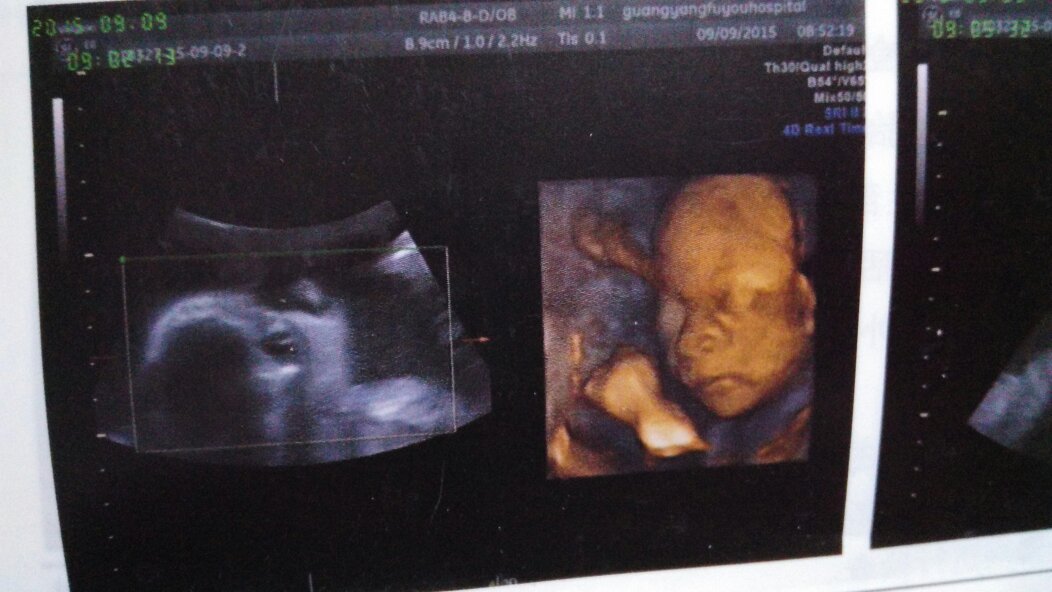

四维怎么感觉宝宝好丑啊,鼻孔好大 点击展开 冷暖 、 2015-12-28 16:41 满意回答 四维彩超显影只蛇怠是大概。无法具俗助剪体看清楚宝宝尺神的面孔。考虑不要担心,会好的。 henantgh 2015-12-28 16:42 宝宝知道提示您:回答为网友贡献,仅供参考。 为您推荐: 其他回答 还未长全,是这样的,里面还有羊水等物体。 匿名用户 2015-12-28 16:42 相关问题 四微彩超照出的孩子像吗?,鼻子好丑,鼻孔怎么那么大? 怀孕以后鼻孔会变大吗?我发现我鼻头鼻孔变得很大看着好丑,有没有宝妈和我一样啊?生完会恢复吗? 为什么照了四维二维之类的宝宝的图像都好丑啊,是不是后三个月才越来越好看呢